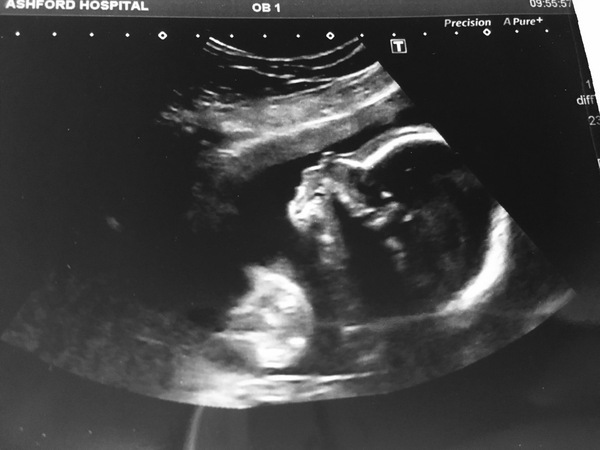

I had my scan this morning and we're team blue again! Smile

All well with the baby, we talked a little about my fear of having an even bigger baby this time & she checked baby's measurements against DS1's (which had actually been stored on a computer system rather than paper!) and she said that DS1 was measuring bigger at the 20wk scan so I guess that's a small reassurance. Also confirmed that baby is a right wriggler....but then I already new that! Only managed to get a pic of the head....